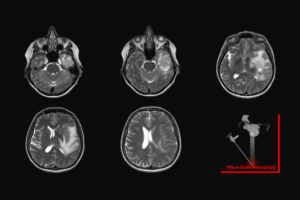

Beyin tümörü ameliyatı, tümörlü dokunun dikkatle çıkarılarak beyin fonksiyonlarının korunmasını ve hastanın yaşam kalitesinin artırılmasını amaçlayan ileri düzey bir cerrahi girişimdir.

Beyin ameliyatı, hastalığın türüne ve yerine göre mikrocerrahi yöntemlerle kafatasında açılan bir pencere aracılığıyla beyin dokusuna ulaşılarak gerçekleştirilen hassas bir cerrahi işlemdir.

Kronik subdural kanama, genellikle hafif kafa travmaları sonrası beyin zarları arasında yavaşça kan birikmesiyle oluşan ve baş ağrısı, dengesizlik, unutkanlık gibi belirtilerle ilerleyen ciddi bir beyin kanaması türüdür.